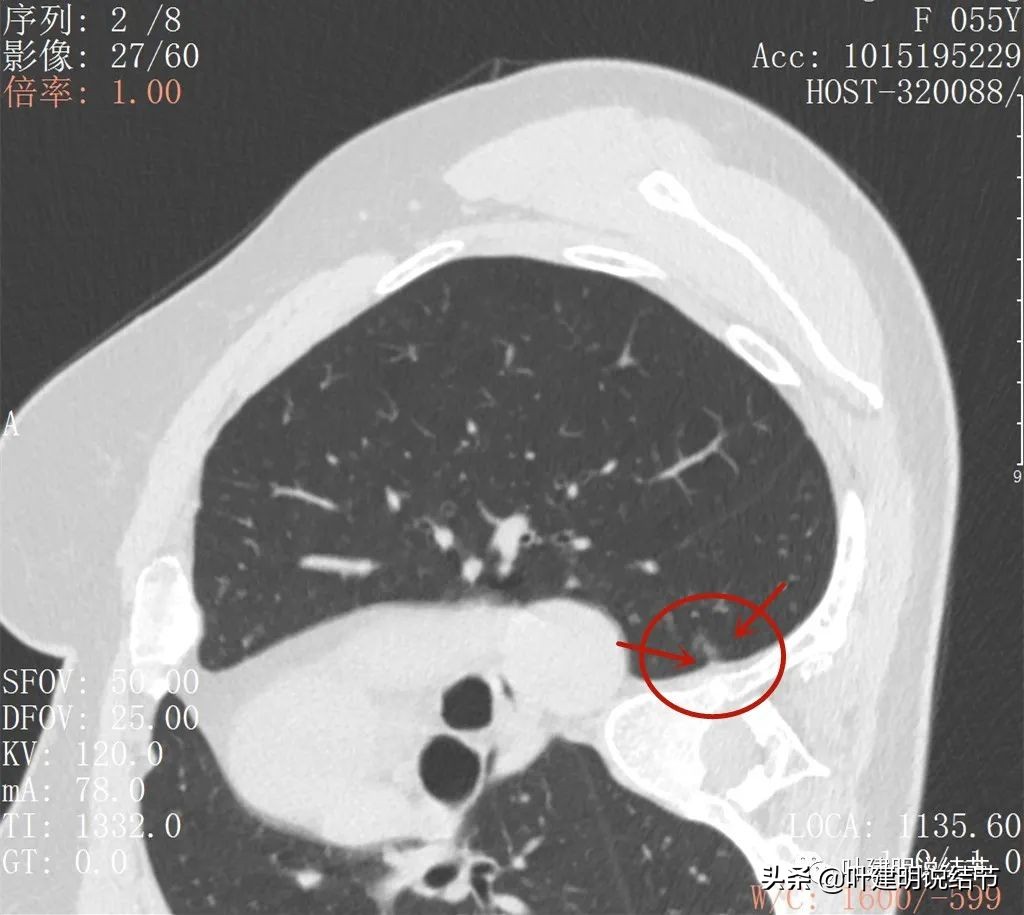

我们先来看她的2021年3月CT图像:

上图是较大的病灶,但密度很低,轮廓较清,但瘤肺边界偏模糊,似见血管进入,由于密度低,风险不大,当时嘱随访。